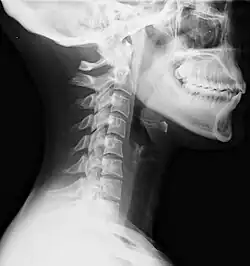

| Lateral view X-ray of whiplash showing a loss of normal lordosis of the cervical vertebrae | |